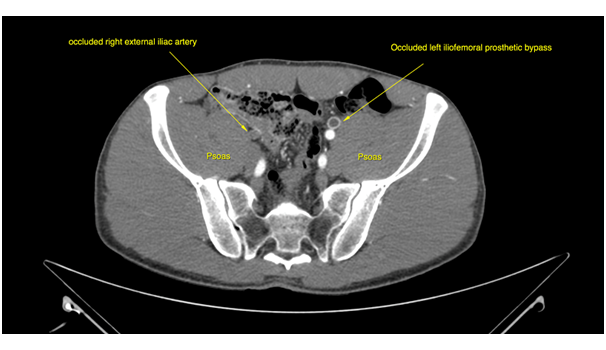

One year later he was visited for the appearance of ischemic symptoms in the right lower limb, calf claudication, pulselessness and subtle pallor, with no critical ischemia signs. An emergency duplex ultrasound evaluation showed a pathological Doppler curve and lowered systolic blood flow speed in the right femoral artery thus suggesting iliac stenosis. With the diagnostic orientation of a complicated right EIA endofibrosis, low molecular weight heparin was prescribed to avoid progressive thrombosis and a new angio CT scan was performed. The CT scan demonstrated an acute thrombosis of the right EIA, with patency of the previously revascularized left EIA, and an endovascular revascularization was programmed (Figure 1) (Figure 2).

Figure 2 CT scan oblique reconstruction showing occlusion of the right EIA, the occluded iliac prosthetic graft and patency of the native left iliac arteries after revascularization.